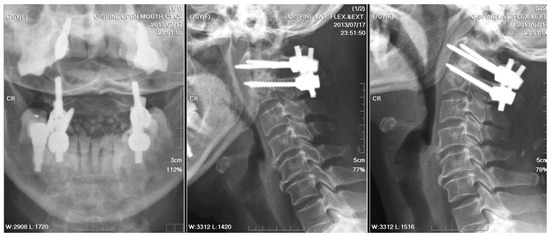

A C2 odontoid biopsy was performed via a transoral approach to confirm the diagnosis, revealing chronic granulomatous inflammation with acute inflammatory changes in the soft tissue. A nonfermenting Gram-negative bacillus was identified by Gram staining, but the result of the AFB test for TB was negative. Co-trimoxazole was administrated postoperatively for a week, followed by a 5-week demonstration of ampicillin/sulbactam. After posterior fusion with bilateral C1 lateral mass and C2 transpedicular screw fixation, stabilization was achieved for AAI (Figure 3). The patient recovered well after surgery, with a significant alleviation of symptoms. The patient received cervical spine plain radiographs and follow-up visits at the neurosurgery outpatient department every three months.

Figure 3. Postoperative radiographs of the cervical spine: They were checked three weeks after a five-week course of antibiotics and posterior instrumented fusion with bilateral C1 lateral mass and C2 transpedicular screw fixation. The stabilization was fair.